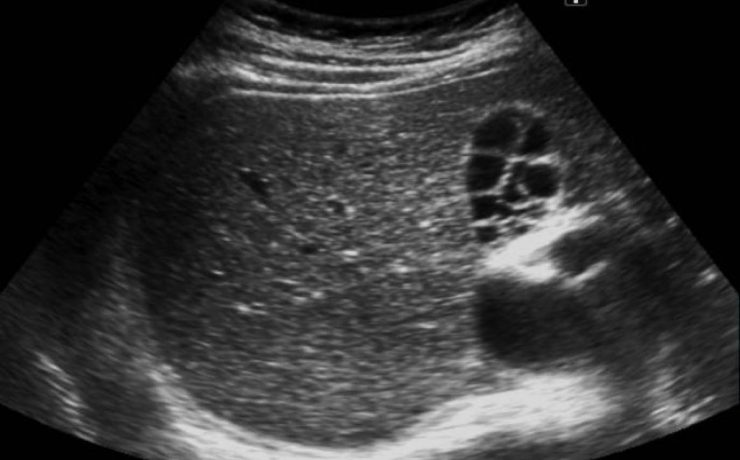

Los bultos o anormalidades en la mama generalmente se detectan por medio de un examen físico, mamografía, u otros estudios de diagnóstico por imágenes. Sin embargo, no siempre es posible detectar a través de dichos diagnósticos por imágenes si el crecimiento de los mismos es cancerígeno o benigno. Una biopsia